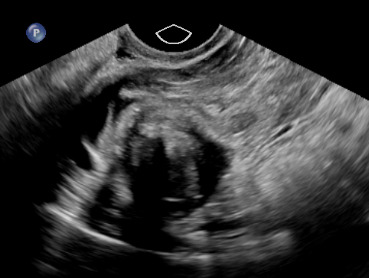

On exam, her vital signs were within normal limits. Abdominal exam revealed significant tenderness to palpation throughout the lower abdomen along with rebound tenderness. Laboratory evaluation revealed a hemoglobin of 11.9 g/dL and β human chorionic gonadotropin of 1,686 mIU/mL. Transabdominal and transvaginal ultrasound revealed a normal appearing uterus measuring 9.6 x 5.0 x 5.5 cm with no identified intrauterine gestational sac or yolk sac. There was noted to be a non-specific heterogenous, nonvascular mass of the right adnexa with no pelvic free fluid noted (Figure 1).